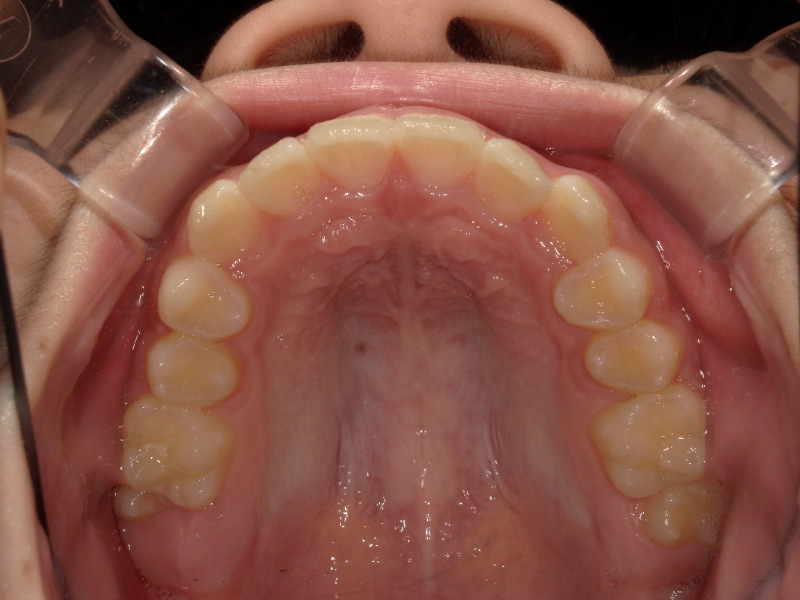

始めの検査の時の写真です。

上の歯の矯正

過去にこの男の子は他院で上の歯並びのみ矯正をしていました。

確かに上の歯は綺麗ですが、下の歯にはガタつきが残っています。

この時既に歯の生え変わりは終わっており全て永久歯の状態です。